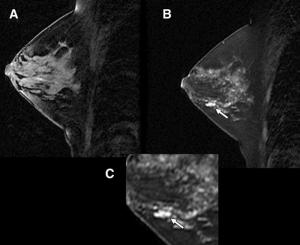

Breast cancer detection rates increase substantially when women at high risk and those with dense breasts undergo mammography and ultrasound annually, according to a study presented Wednesday at the 2009 RSNA meeting. MRI is an even more effective technique when used with mammography, but only for women who are at high risk for the condition.

Targeted breast ultrasound is less invasive and expensive than biopsy, as well as reduces anxiety over breast cancer screening.